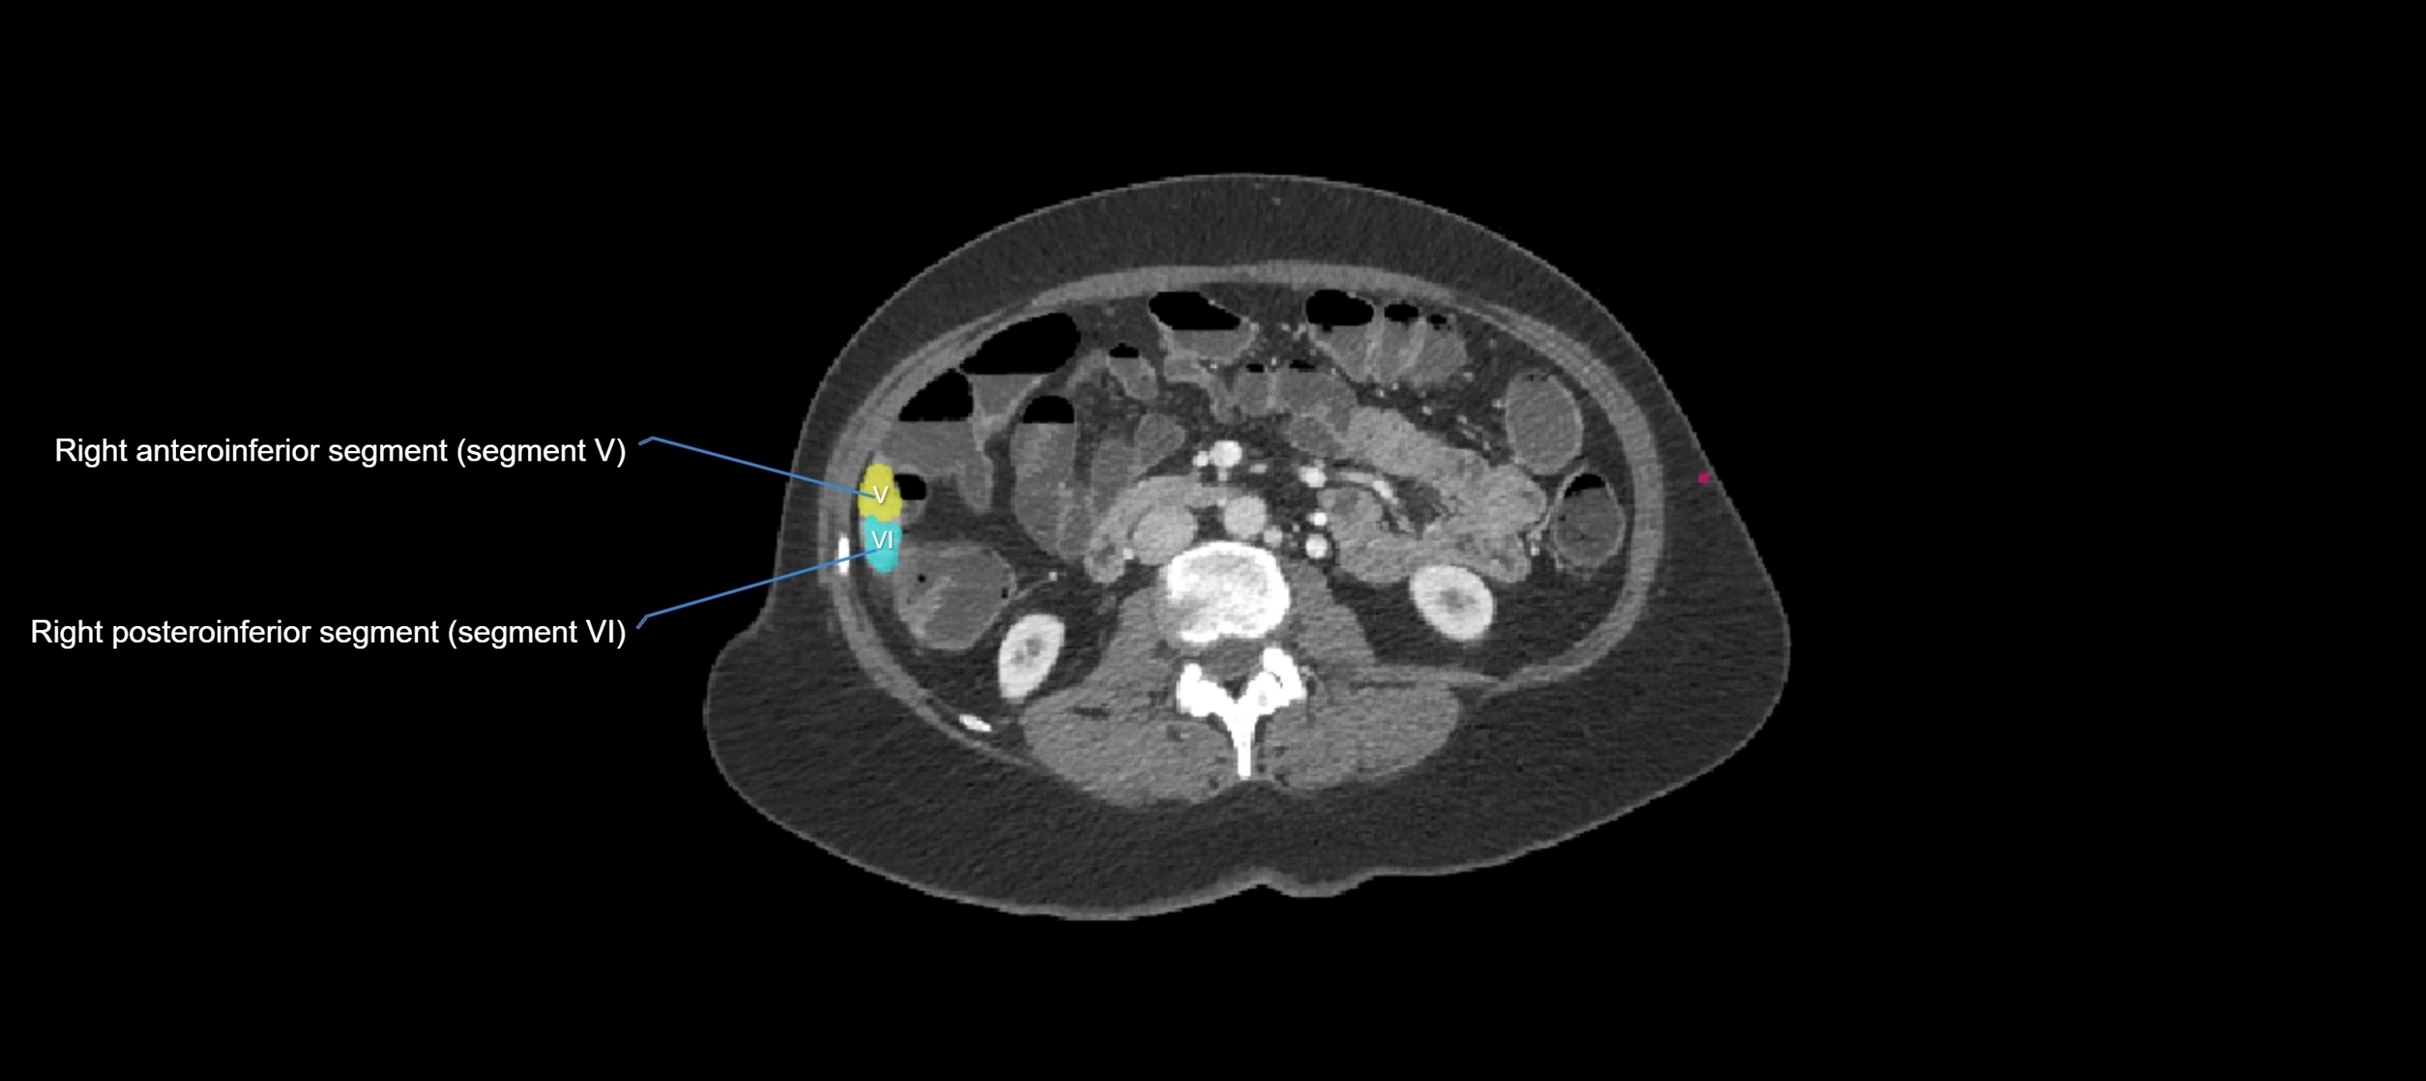

CT Image

image